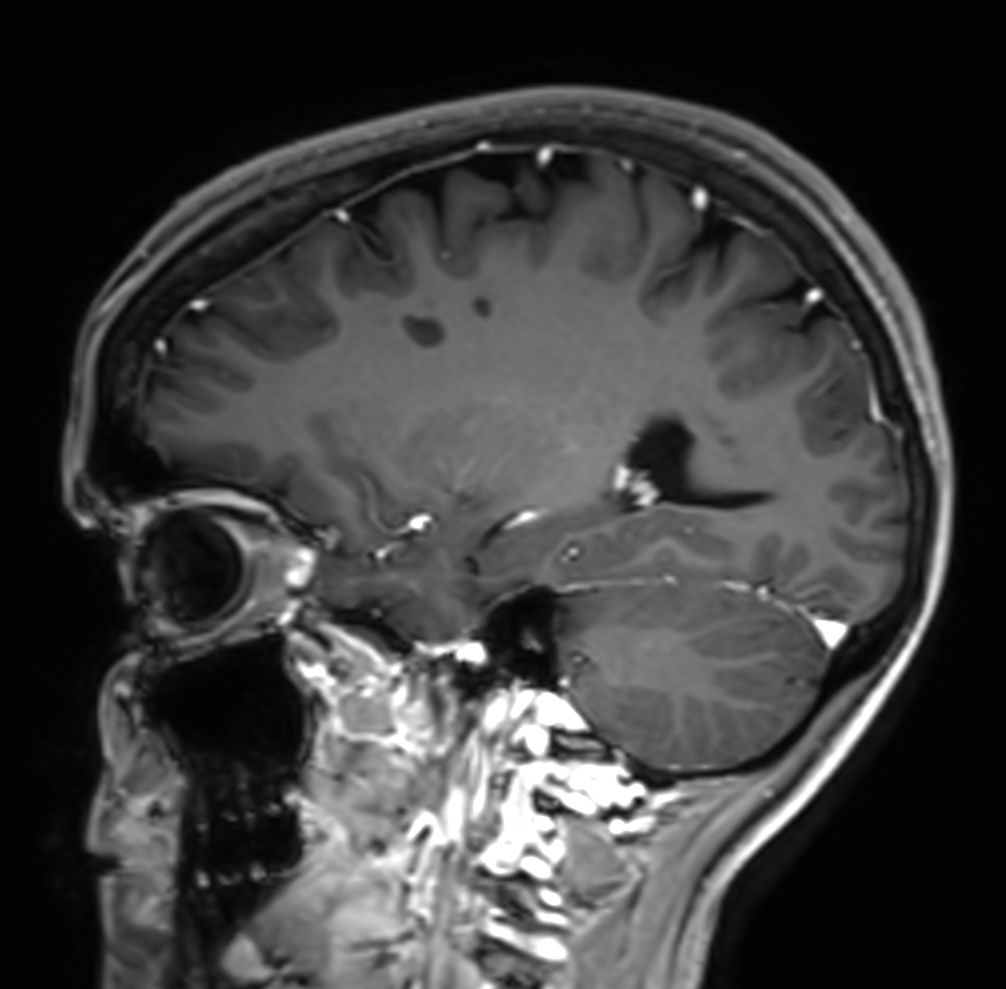

SWI sequence has a high sensitivity to enhance contrast for deoxygenated (venous) blood or calcium deposits. This may help, when used in combination with other clinical information, in the diagnosis of various neurological pathologies. 3D imaging lets you acquire high resolution data in multiple directions in one scan. Isotropic voxel size enables reformats in any plane without loss of resolution. FLAIR* requires offline post processing combining the contrast of 3D FLAIR and 3D SWI EPI into a single image. This enables the visualization of Central Vein Sign, mapping subcortical veins onto 3D FLAIR contrast images.